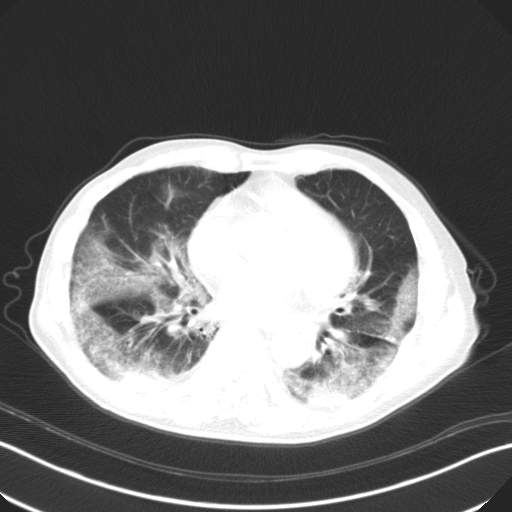

In this study, we leveraged GSInquire [39] to perform explainability-driven performance validation of COVIDNet-CT in order to better understand its decision-making behaviour, and to ensure that its decisions are based on diagnostically-relevant imaging features rather than irrelevant visual indicators. Figure 7 shows the critical factors identified by GSInquire in three chest CT images of patients with COVID-19 pneumonia. Examining these visual interpretations, we observe that COVIDNet-CT primarily leverages abnormalities within the lungs in the chest CT images to identify COVID-19 cases, as well as to differentiate these cases from non-COVID-19 pneumonia cases. As previously mentioned, our initial experiments yielded deep neural networks that were found via explainability-driven performance validation to be basing their detection decisions on irrelevant indicators such as patient tables and imaging artifacts, which highlights the importance of leveraging explainability methods when building and evaluating deep neural networks for clinical applications. Furthermore, the ability to interpret how COVIDNet-CT detects COVID-19 cases may help clinicians trust its predictions, and may also help clinicians discover novel visual indicators of COVID-19 infection which could be leveraged in manual screening via CT imaging.

Figure 7: Example chest CT images of COVID-19 cases and their associated critical factors (highlighted in red) as identified by GSInquire [39].